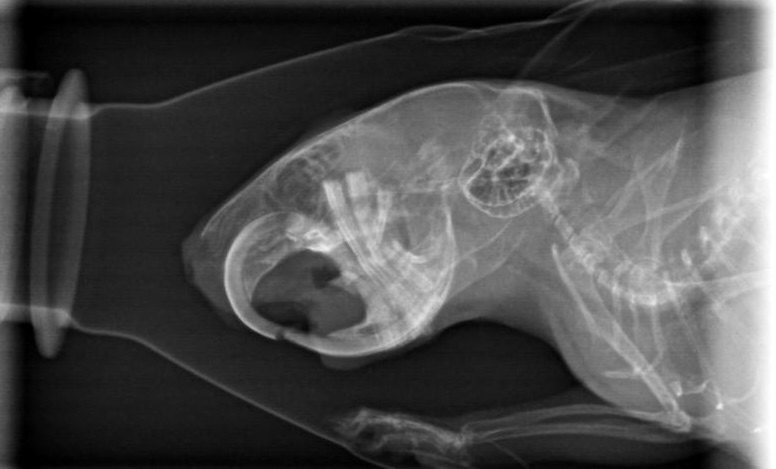

heute gab es doch ein Kontrollröntgen.

Gerade weil es vor Weihnachten super stressig ist, hab ich gesagt sie sollens nur machen, wenns zeitlich rein passt. Und hat es wohl

Hier könnt ihr mit gucken:

Der Unterschied zwischen diesen und den ersten Bildern beträgt übrigens 2 Monate (und ein Tag)

Wow, ohne davon wirklich Ahnung zu haben, sieht man auf den beiden Fotos von oben geröntgt sehr deutlich die positive Entwicklung

… das habt ihr toll hingekriegt